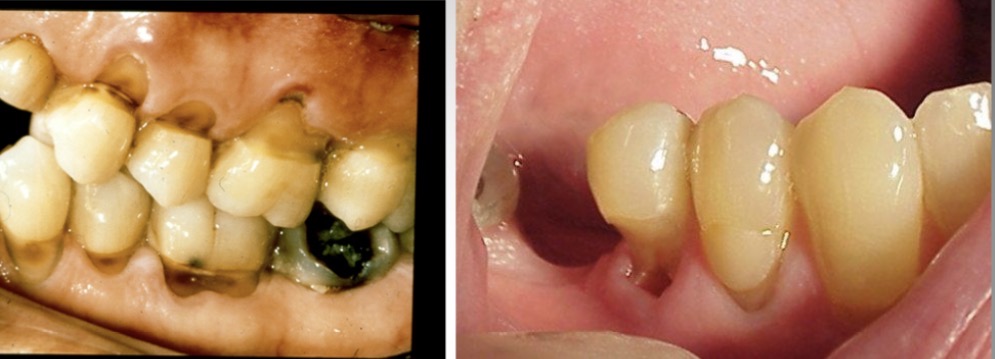

Dentinogenesis imperfecta

-calcified pulp chambers; bell shaped teeth; this is a hereditary disorder.

-This condition is sometimes correlated with osteogenesis imperfecta